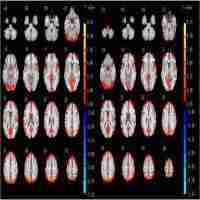

| Description | Journal: Human brain mapping Characterization of large‐scale brain networks using blood‐oxygenation‐level‐dependent functional magnetic resonance imaging is typically based on the assumption of network stationarity across the duration of scan. Recent studies in humans have questioned this assumption by showing that within‐network functional connectivity fluctuates on the order of seconds to minutes. Time‐varying profiles of resting‐state networks (RSNs) may relate to spontaneously shifting, electrophysiological network states and are thus mechanistically of particular importance. However, because these studies acquired data from awake subjects, the fluctuating connectivity could reflect various forms of conscious brain processing such as passive mind wandering, active monitoring, memory formation, or changes in attention and arousal during image acquisition. Here, we characterize RSN dynamics of anesthetized macaques that control for these accounts, and compare them to awake human subjects. We find that functional connectivity among nodes comprising the “oculomotor (OCM) network” strongly fluctuated over time during awake as well as anaesthetized states. For time dependent analysis with short windows (<60 s), periods of positive functional correlations alternated with prominent anticorrelations that were missed when assessed with longer time windows. Similarly, the analysis identified network nodes that transiently link to the OCM network and did not emerge in average RSN analysis. Furthermore, time‐dependent analysis reliably revealed transient states of large‐scale synchronization that spanned all seeds. The results illustrate that resting‐state functional connectivity is not static and that RSNs can exhibit nonstationary, spontaneous relationships irrespective of conscious, cognitive processing. The findings imply that mechanistically important network information can be missed when using average functional connectivity as the single network measure. Hum Brain Mapp 34:2154–2177, 2013. |